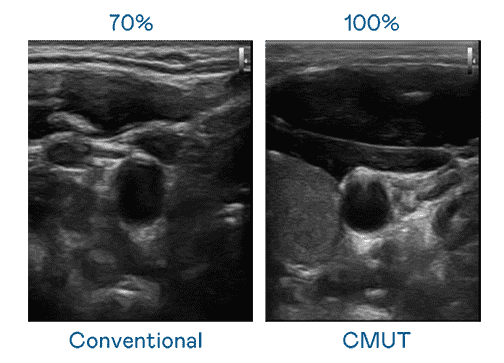

CMUT 技术是一种用电容式微机电元件来产生超音波讯号的技术。。。。与传统 PZT 压电式技术相比,,,,CMUT 频宽增加 30%,,,,更宽频的超音波讯号让影像解析度大幅提升,,,是实现高影像品质医疗超音波扫描、、促进精准医疗发展的关键技术。。。

大频宽带来超清晰影像

超音波影像的解析度高低,,,,首先取决于探头能发出的讯号频宽。。。云顶国际8588yd CMUT 可提供高清晰的超音波讯号,,提供高频宽、、、高灵敏度、、、、影像纹理细节更高的超音波影像,,,协助医护人员缩短影像判读时间及利用精准的医疗影像进行诊断。。。。